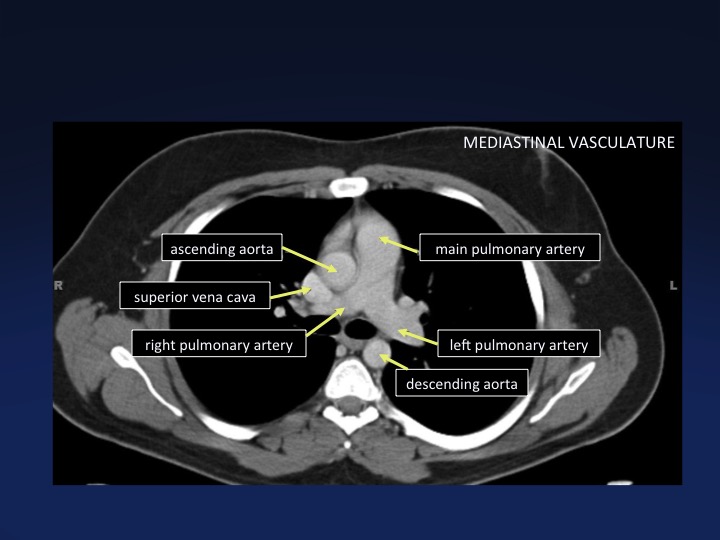

Chest Anatomy Mri Chest Thorax Axial Anatomy Free Cross

Chest Anatomy Mri Chest Thorax Axial Anatomy Free Cross

Chest Ct Cross Sectional Anatomy Cellular And Molecular

Chest Ct Cross Sectional Anatomy Cellular And Molecular